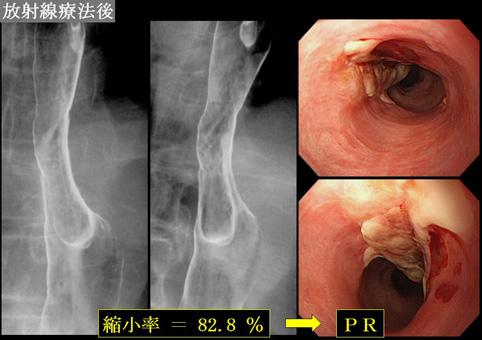

A case of esophageal carcinosarcoma which reduced in size by radiation therapy.

Fukuoka Pref., 큐슈의료센터 (平賀聖久先生、古谷清美先生、村中光先生からの提供症例)